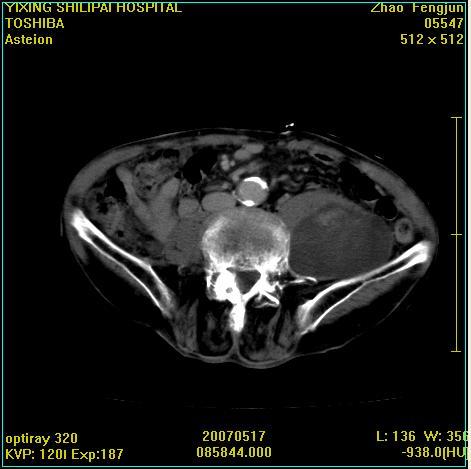

考虑:1、左侧腰大肌囊实性占位性病变(囊性神经根鞘瘤?);

2、右侧兰尾区囊性占位性病变(兰尾囊肿?囊腺癌?类癌?)

以下是引用xiaoniu在2007-5-26 10:45:00的发言:[br]腰大肌的病变应该没有问题,增强扫描还有轻度强化及细小血管影入内,应该排除脓肿,考虑占位性病变,腰大肌的占位多考虑:神经源性肿瘤。另外腹主动脉下端有真假腔的强化,考虑:主动脉夹层。[br][br][本贴已被 xiaoniu 于 2007-5-26 10:46:39 修改过]

以下是引用老爱克斯新网客在2007-5-26 18:26:00的发言:[br]1左下腹囊实性占位肿块,增强后不均匀强化,位于脊柱旁,椎体骨质无破坏软组织无肿胀,考虑神经源肿瘤神经鞘瘤可能大,2右下腹囊性占位性病变,增强后囊壁强化,考虑阑尾囊肿或囊腺瘤,